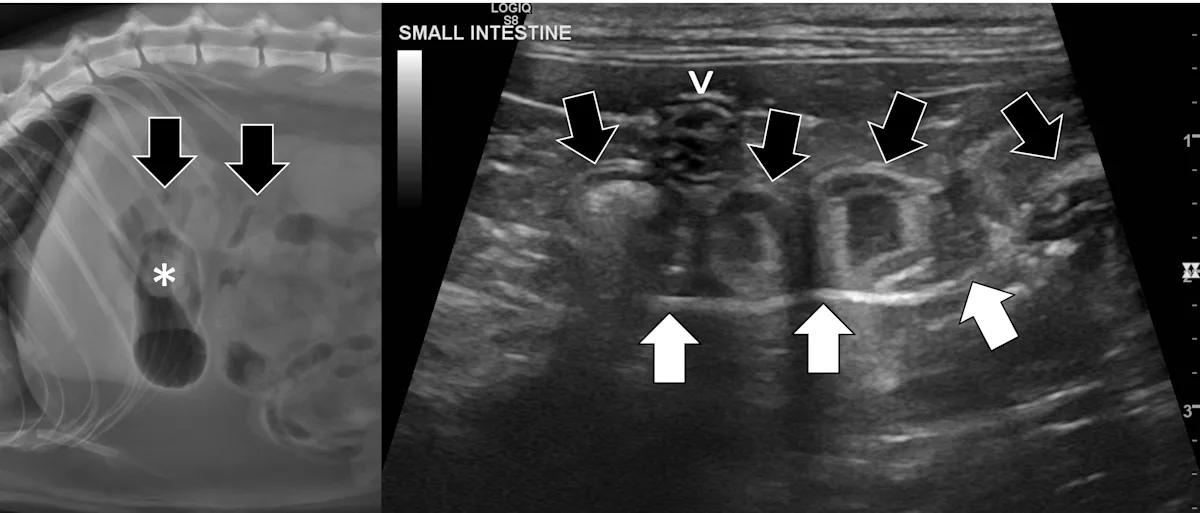

Small Intestinal Mechanical Obstructions

Small intestinal mechanical obstructions occur when a foreign body blocks the lumen of any segment of the small bowel, causing segmental dilation located orad to the foreign body (Figure 3).9-12 As the small bowel increases in size, it crowds the peritoneal cavity and begins stacking on itself with sharp, hairpin turns.9-12 Dilated portions of the small bowel usually contain a mixture of fluid and gas. One study demonstrated that a serosal-to-serosal jejunal diameter of >1.5 cm helped discern dogs with and without mechanical obstruction.1 Dilated bowel can often be followed to the site of obstruction, where it immediately normalizes aborad to the foreign body. In some patients, the foreign body may not be visualized if located deep to more superficially located gas-dilated intestines. In patients scanned in dorsal recumbency, gravity may cause heavier foreign bodies to settle deep in the abdomen. If jejunal dilation >1.5 cm is present but the site of obstruction is not initially seen, the patient may be shifted into right and then left lateral recumbency and the midabdomen reinterrogated. In addition, one study suggested that a foreign body may be palpated in a majority of cases13; physical examination may therefore expedite ultrasonography. If the foreign body can be manually held or trapped against the body wall, ultrasonography can be performed on that location; however, identifying the site of obstruction is not always necessary if segmental dilation is present and the clinical picture supports a diagnosis of mechanical obstruction.

Abdominal ultrasound of a 9-month-old spayed Australian cattle dog with a surgically confirmed small intestinal mechanical obstruction. There is moderate small intestinal dilation (asterisk) with hyperechoic fluid, ingesta, and gas measuring 2.1 cm in diameter at the level of the white calipers oral to a pecan foreign body (pound sign) that is visible as a hyperechoic surface with distal acoustic shadowing. The small intestine is normal and not dilated immediately aboral to the foreign body (arrow), with a small volume of intraluminal gas causing reverberation artifact.